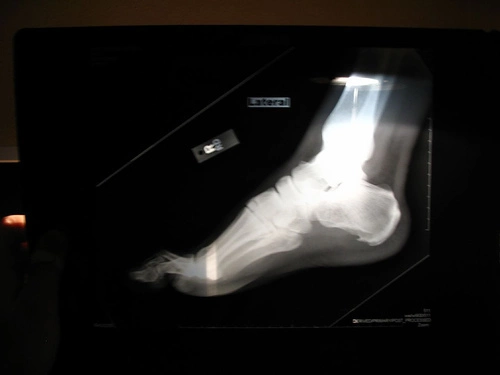

Los esguinces del tobillo resultan del desplazamiento hacia dentro o hacia fuera del pie, distendiendo o rompiendo los ligamentos de la cara interna o externa del tobillo.

La gravedad de la lesión va desde el grado I, en el que la distensión del ligamento es mínima (no se rompen las fibras), al grado III, en el que hay rotura completa. ¿Que ejercicios podemos realizar una vez finalizada la fase médica?.